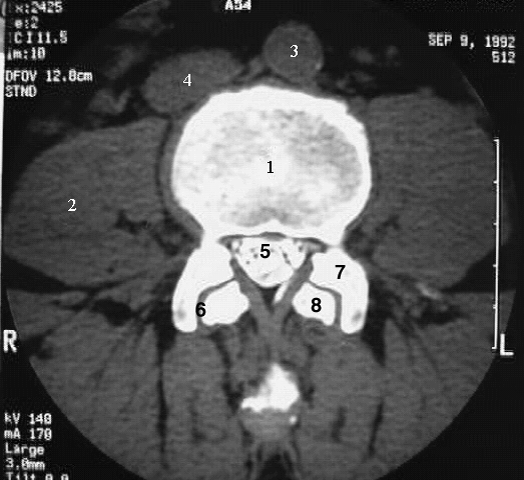

Back-L3 CT after myelography:

1. Vertebral body

2. Psoas major

3. Aorta

4. Inferior vena cava

5. Nerve rootlets of cauda equina

6. Facet joint

7. Superior articular process

8. Inferior articular process.